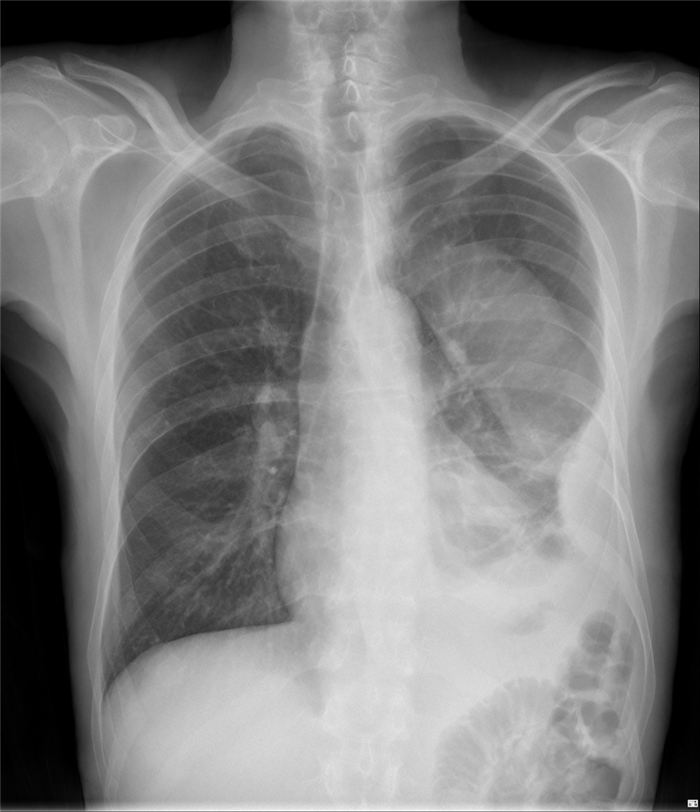

Рентгеновский снимок грудной клетки в прямой проекции следует выполнять у постели больного, чтобы контролировать положение трубки. Если есть сомнения относительно расположения или функционирования плевральной дренажной трубки, следует получить результаты переднезадней и боковой рентгенографии грудной клетки или КТ грудной клетки.

Плевральная дренажная трубка удаляется по мере разрешения процесса. При пневмотораксе аспирацию прекращают, а трубку сразу же помещают на несколько часов в контейнер с водой, чтобы убедиться в том, что весь воздух вышел, а легкое остается расправленным. Перед снятием дренажной трубки после полученного последнего подтверждения просачивания воздуха через 12 и 24 часов часто повторно проводят рентгенографию грудной клетки. При наличии плеврального выпота или гемоторакса трубка, как правило, удаляется при снижении количества дренируемой серозной жидкости до

Через несколько часов после удаления плевральной дренажной трубки следует повторно провести рентгенографию грудной клетки. Если на рентгенограмме грудной клетки после извлечения плевральной дренажной трубки пневмоторакс не наблюдается, в дальнейшем проведении рентгенографии грудной клетки нет необходимости, за исключением случаев, которые продиктованы клиническими изменениями в состоянии пациента.